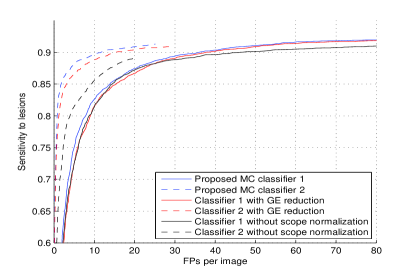

The proposed CAD were first evaluated on a separate GE Senographe projection image dataset with and truthed biopsy-proven malignant MCs and MC groups. The candidate generator provided sensitivity to individual MCs with FPs per image. Figure 3 shows the free-response receiver operating characteristic (FROC) curves of the test set from the outputs of the three pre-trained classifiers.

To test the system robustness with respect to unseen data, all GE projection images and their counterparts with subtracted local means were removed from the training set. This reduced about of all the positive training samples. The FROC in red curve in Figure 3 shows that the system still keeps a high sensitivity rate even with this smaller training dataset.

The black FROC curves were generated from training features without scope-based normalization. Instead, only a global entire breast region based normalization was used for each image. Especially, the FROCs in Figure 3(a) show the strength of the scope-based normalization to increase the robustness of both appearance features and consistency measurement features.